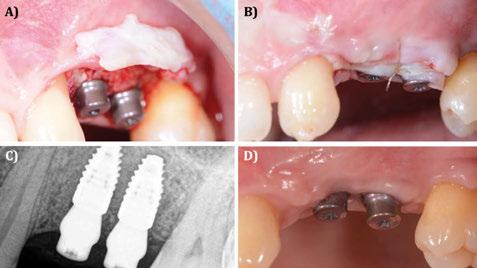

Figura 28. Caso clínico tratado mediante injerto óseo de lámina alogénica (Cortical Plate Salugraft®). A) Situación clinical basal. B) Situación radiográfica (3D) basal en posición de 45. C) Situación radiográfica (3D) basal en posición de 46. D) Extracción de 45 y elevación del colgajo a espesor total. E) Fijación de las láminas alogénicas (Cortical Plate Salugraft®) vestibular y oclusal.

Figura 29. Caso clínico tratado mediante injerto óseo de lámina alogénica (Cortical Plate Salugraft®). Continuación. A) Vista vestibular de la lámina vestibular. B) Vista oclusal de la lámina oclusal con un injerto de tejido conectivo autólogo en la zona de la extracción. C) Sutura y cierre primario del procedimiento. Vista oclusal. D) Sutura y cierre primario del procedimiento. Vista vestibular.